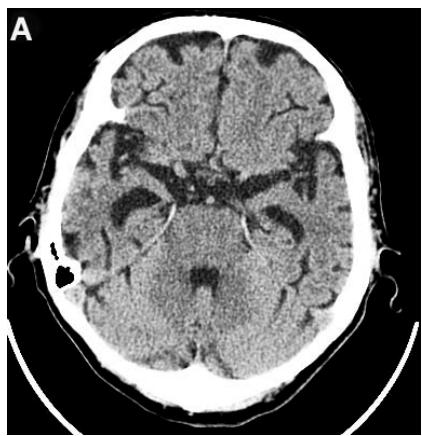

Figure 4: Same patient P., 75 years old, female TDR-3.

A. Cerebral CT before transcatheter intracerebral laser PBMT: Total atrophy of the temporal lobes is $40\%$ of the total tissue volume (TDR-3). B. Cerebral CT 12 months after transcatheter intracerebral laser PBMT: Reduction of the total atrophy of the temporal lobes by $12\%$. The patient is transferred to AD group in TDR-2 stage.

Accordingly, 5 (71.43%) patients were transferred to TDR-2 group, 2 (28.57%) patients remained in TDR-3 group (Table 2).

According to the results of digital processing of CT and MRI images one year after the treatment, all 7 (100%) patients had a decrease in the atrophy of the cerebral temporal lobes. It was accompanied by narrowing of the Sylvian fissures and subarachnoid space. Of these, 5 (71.43%) patients had a 10-12% decrease (Figures 4A, 4B), and 2 (28.57%) a 6-8% decrease.